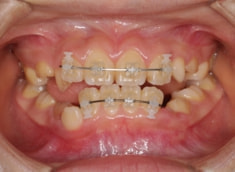

治療後(1年5ヶ月後)